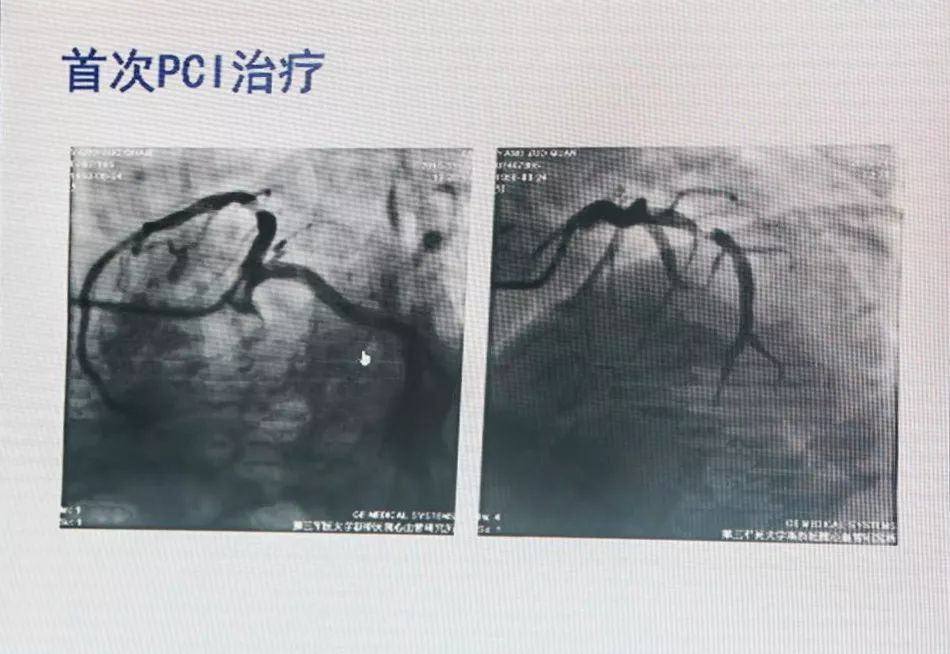

65岁,男性,以“劳力性胸闷胸痛3年,加重11天”入院。

既往糖尿病病史2年,未规律用药;脑梗死病史4年,现遗留步态不稳,未规律用药。

8日后再次胸痛

18:00患者外出就餐突发胸痛,持续不能缓解;

当地人民医院诊断考虑“急性心肌梗死”;

联系陆军军医大学第二附属医院胸痛中心,考虑亚急性支架内血栓形成,绕行急诊,PPCI。

分析血栓形成原因,可能是患者术后自行停用DAPT,支架贴壁不良等。